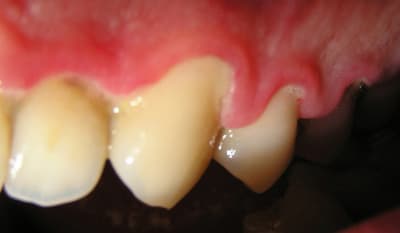

J'ai ressorti les photos prises initialement:

22/06/2005 à 02h01

...Et les photos prises aujourd'hui, juste avant la séance de démonstration du contrôle de plaque.